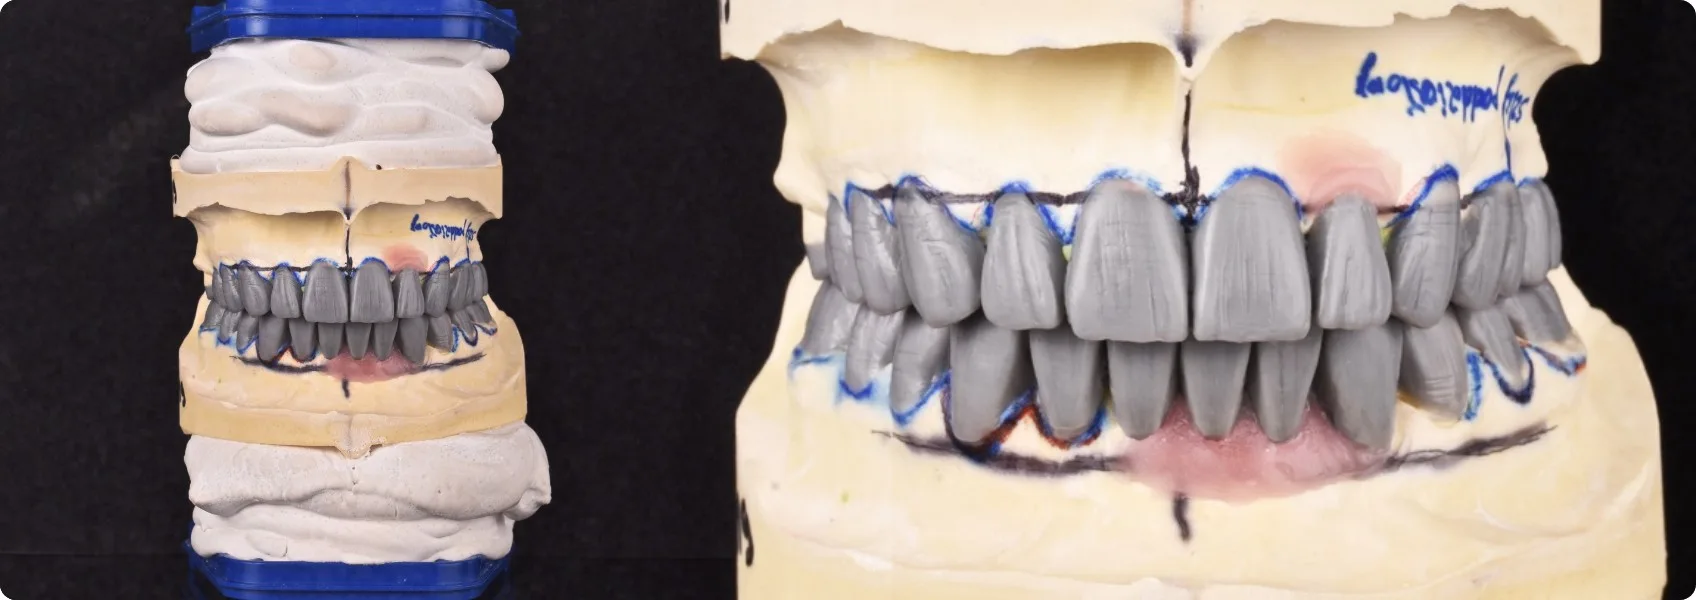

Jednym z pierwszych etapów w tak złożonym leczeniu jest wax-up. To model przyszłego uśmiechu Pacjenta, wykonany przez technika dentystycznego na podstawie precyzyjnych wytycznych od protetyka.

Na gipsowym modelu odzwierciedlającym sytuację w ustach Pacjenta, technik z niezwykłą starannością modeluje z wosku przyszłe zęby – ich kształt, wielkość, ustawienie. To jak praca rzeźbiarza!

W niektórych gabinetach protetycy pomijają etap wax-upu. My nigdy. Dzięki wax-upowi zarówno my, jak i Pacjent, możemy zobaczyć i ocenić planowaną odbudowę, zanim jeszcze podejmiemy jakiekolwiek nieodwracalne kroki w jamie ustnej. Leczenie jest bezpieczniejsze i wszyscy wiemy, jak się zakończy. Jeśli protetyk nie robi wax-upu, rezultat pracy jest zaskoczeniem… nie zawsze pozytywnym.

Bez wax-upu nie możemy zrobić próby nowych zębów. Pacjent nie ma szansy zobaczyć się w lustrze z taką przymiarką protezy, nie ma jak zgłosić swoich uwag co do jej wygody czy kształtu.

W przypadku naszego Pacjenta, efekt, który udało nam się osiągnąć już na etapie tego woskowego modelu, przerósł jego najśmielsze oczekiwania. To dało mu ogromną nadzieję i motywację do dalszego leczenia.